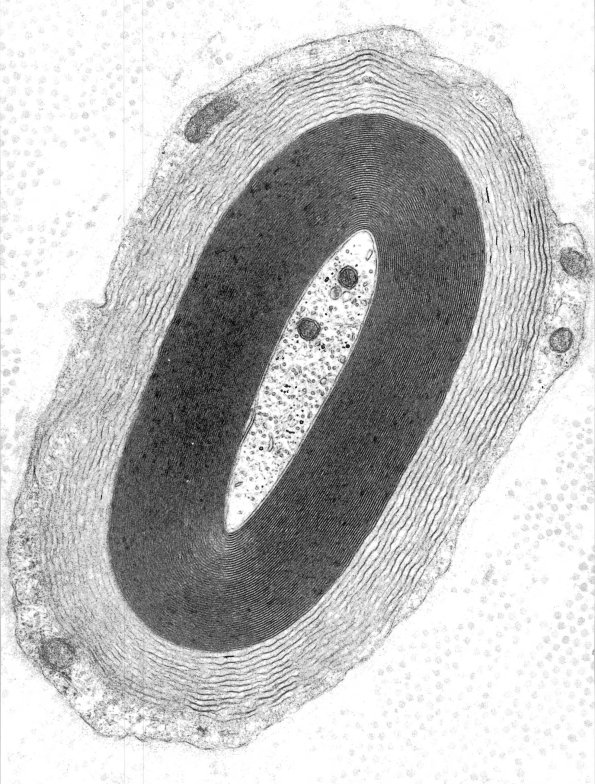

3A1,2 In this case the WSM is difficult to overlook involving nearly a third of the myelin thickness. (electron micrographs)